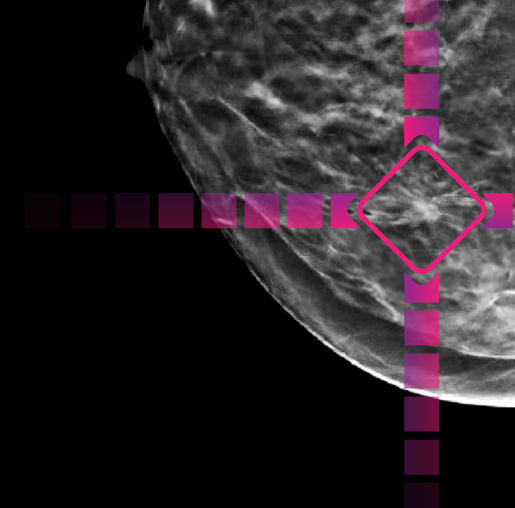

The Enhanced Breast Cancer DetectionTM (EBCDTM) program is a breakthrough in early detection. It uses artificial intelligence to help radiologists detect even subtle lesions. Combined with exceptionally high-quality mammography systems, EBCD's artificial intelligence (AI) optimizes breast cancer screening, giving women greater confidence in their results.

After your exam, Artificial Intelligence (AI) technology2 is applied to your mammogram.

The AI points out areas of interest on your exam to help the radiologist detect very subtle abnormalities.